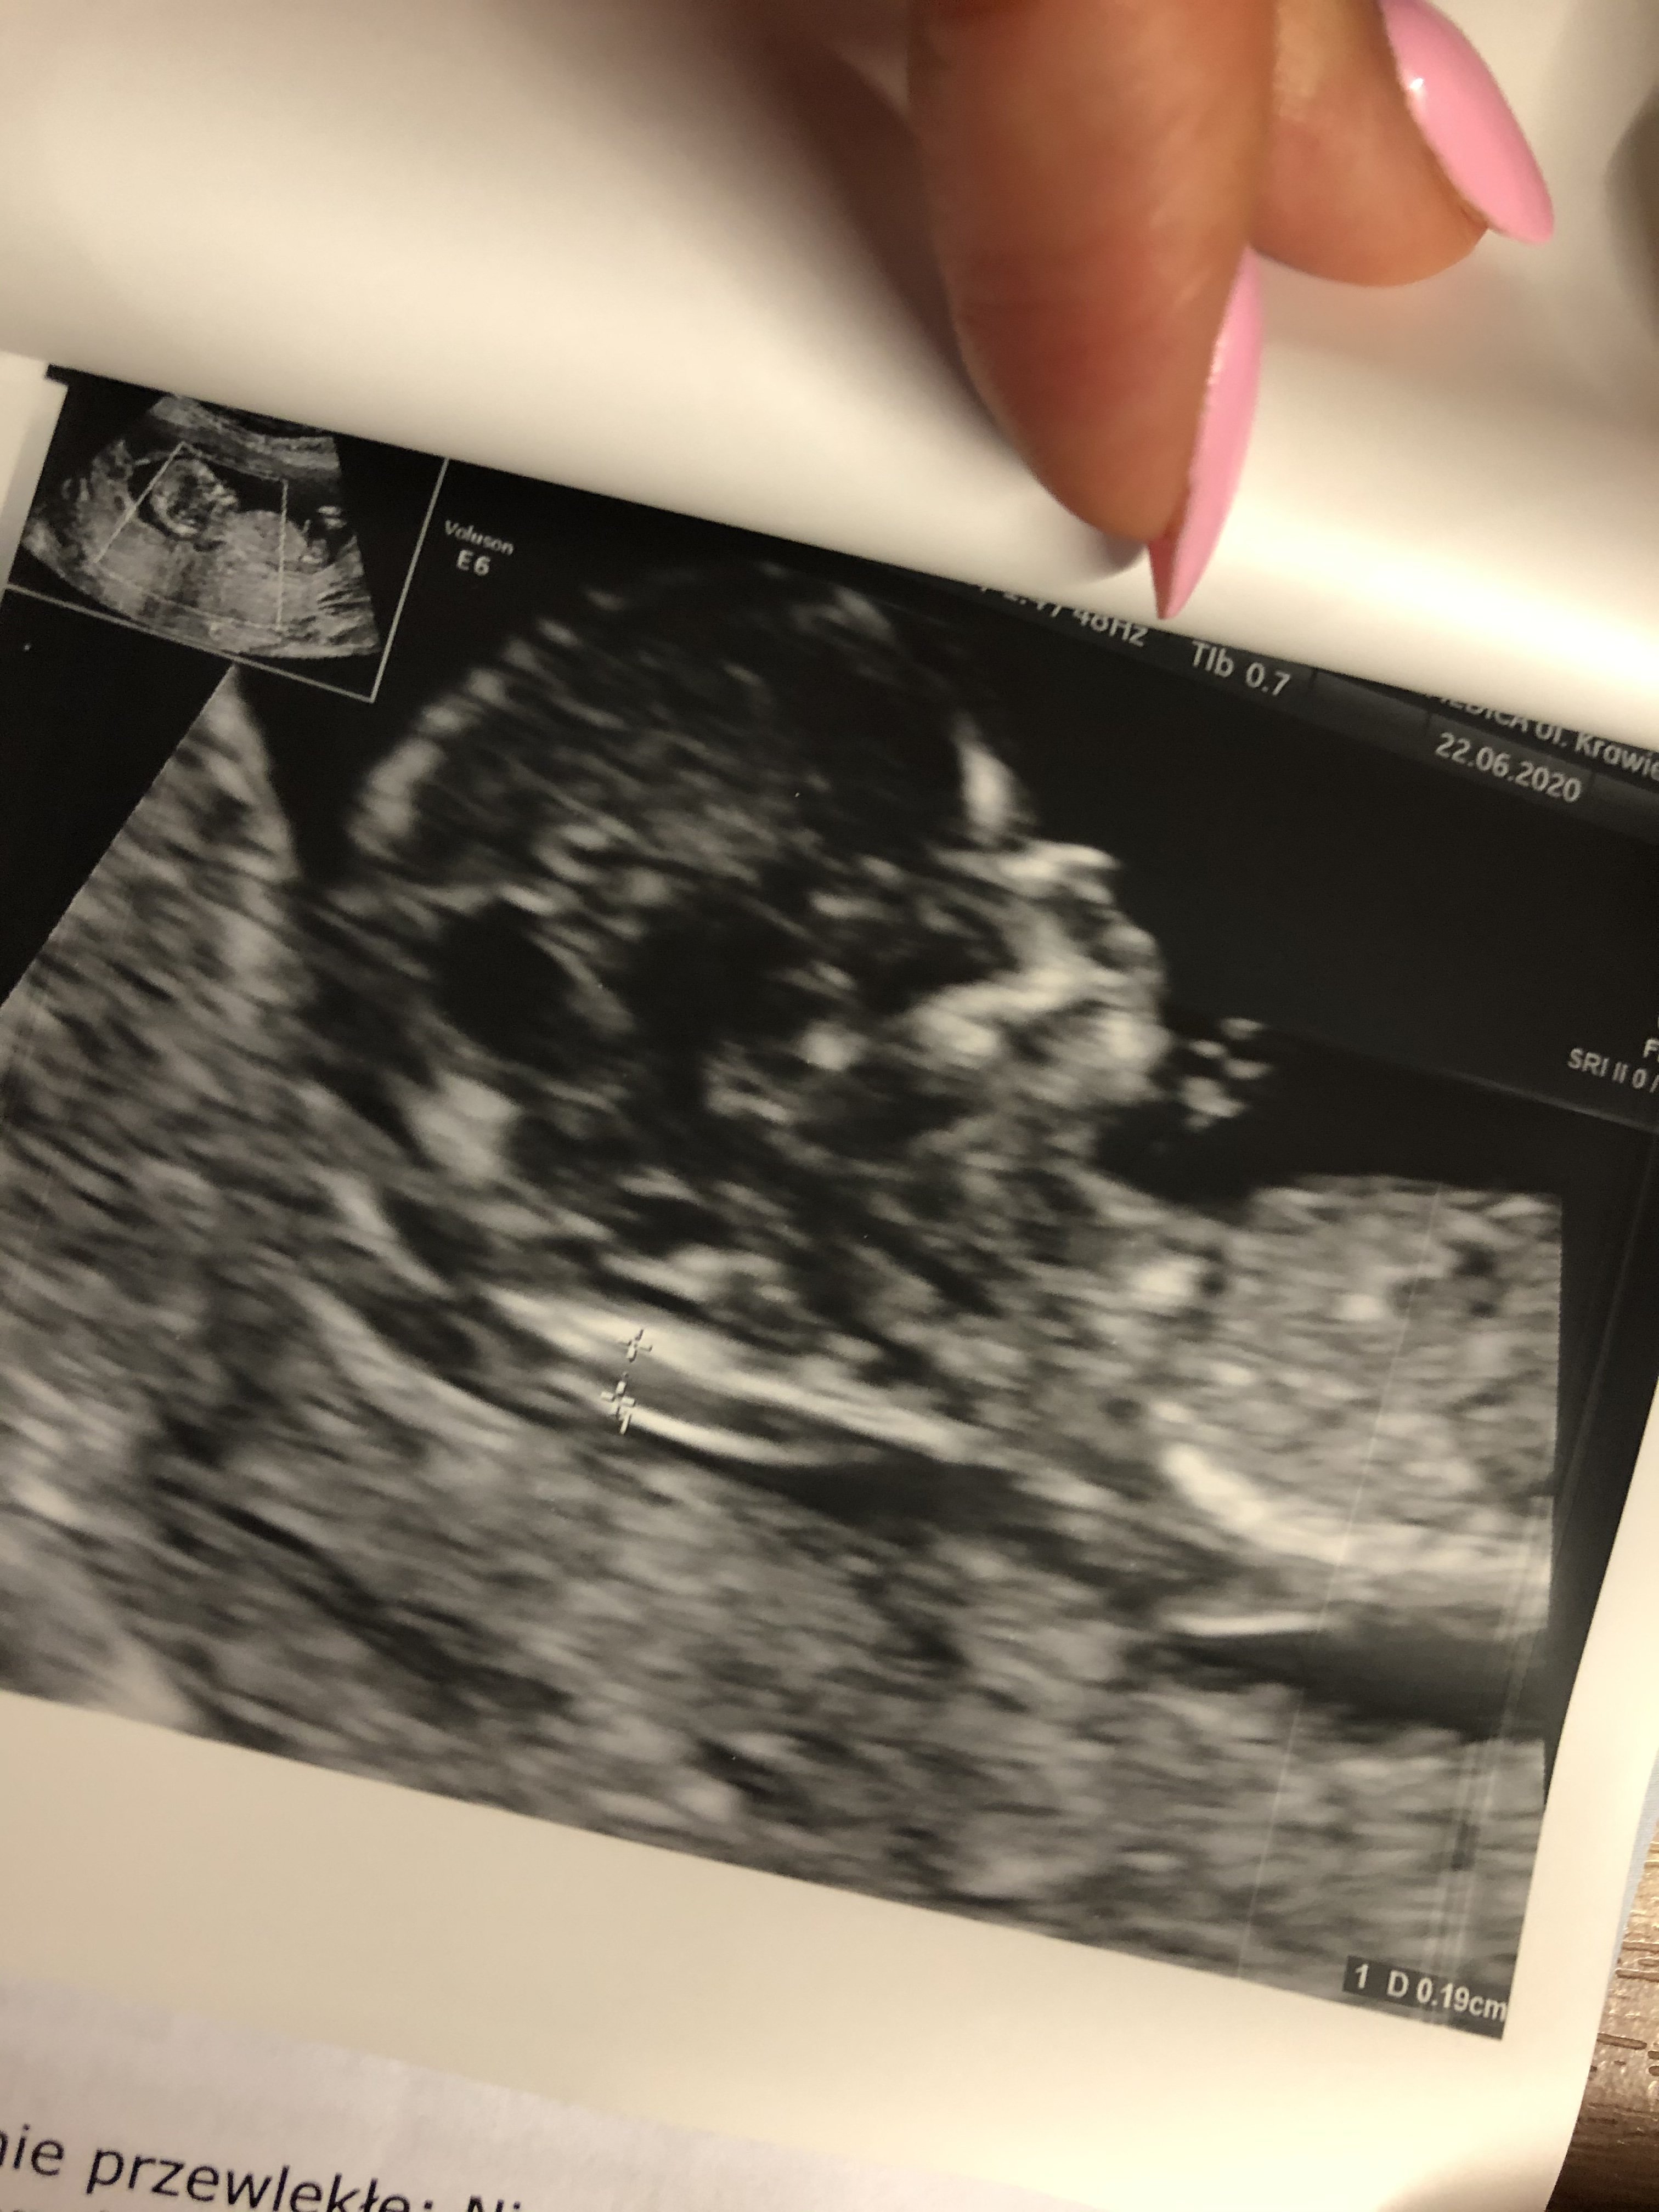

Co do prenatalnych ja chyba (ale jeszcze nie pewne) robię tylko usg. W poprzedniej ciąży miałam tylko usg i to było dla mnie wystarczające. Jeszcze się doedukuje na temat testów z krwi, no ale zobaczymy.